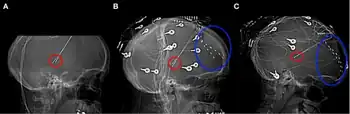

a-c) Thalamic stimulator contacts in red, subdural electrodes in blue. | |